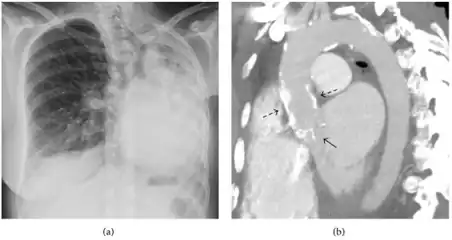

A fibrothorax can typically be diagnosed by taking an appropriate medical history in combination with the use of appropriate imaging techniques such as a plain chest X-ray or CT scan.[3] These imaging techniques can detect fibrothorax and pleural thickening that surround the lungs.[7] The presence of a thickened peel with or without calcification are common features of fibrothorax when imaged.[3] CT scans can more readily differentiate whether pleural thickening is due to extra fat deposition or true pleural thickening than X-rays.[3]

If a fibrothorax is severe, the thickening may restrict the lung on the affected side causing a loss of lung volume.[7] Additionally, the mediastinum may be physically shifted toward the affected side.[3] A reduction in the size of one side of the chest (hemithorax) on an X-ray or CT scan of the chest suggests chronic scarring.[6] Signs of the underlying disease causing the fibrothorax are also occasionally seen on the X-ray.[6] A CT scan may show features similar to those seen on a plain X-ray.[7] Lung function testing typically demonstrates findings consistent with restrictive lung disease.[6]